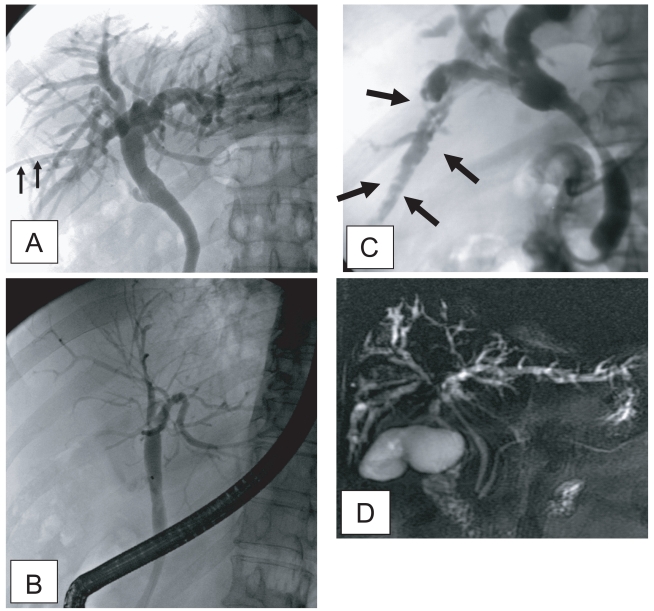

Sonographic findings of diffuse dilatation of the intrahepatic bile ducts and increased periductal echogenicity are known to well reflect pathological changes associated with clonorchiasis (Fig. 2) (Lim et al., 1989; Hong et al., 1994). Sonography is considered a good tool for the diagnosis of clonorchiasis, particularly in cases with a moderate or heavy burden of worms. According to a prior study in Korea, sonography showed low sensitivity and low specificity in the diagnosis of active clonorchiasis (Hong et al., 1998). The study suggested that the low sensitivity was due to a light worm burden and that the low specificity was due to residual pathology after cure.

In a recent study conducted by us in China, increased periductal echogenicity and floating echogenic foci in the gallbladder were proposed as the 2 most significant sonographic findings of active clonorchiasis (Choi et al., 2004). Increased periductal echogenicity represents a thickening of the ductal wall according to mucosal hyperplasia and periductal fibrosis, and the floating echogenic foci indicate worms or desquamated material in the gallbladder (Figs. 2A, B, C) (Lim et al., 1989; Hong et al., 1994; Choi et al., 1999). In our study in China, increased periductal echogenicity showed a sensitivity and specificity for active clonorchiasis of 35% and 91%, respectively (Choi et al., 2004). Floating echogenic foci in the gallbladder had a sensitivity and specificity of 28% and 94%, respectively. However, floating echogenic foci within the gallbladder have been rarely documented in Korea (Lim et al., 1989; Lim, 1990).

In the past literature, diffuse dilatation of the intrahepatic bile ducts on sonographic examination has been considered a hallmark of clonorchiasis (Lim et al., 1989; Lim, 1990; Hong et al., 1994). Diffuse dilatation of the intrahepatic bile ducts was found in an about half (49-52%) of the control subjects in either present endemic area or past endemic area (Fig. 2D) (Hong et al., 1998; Choi et al., 2004). Thus, patients only with a dilatation of the intrahepatic bile ducts detected by sonography cannot be considered candidates for praziquantel treatment (Chen et al., 1994; Hong et al., 1998; Choi et al., 1999). In an experimental study, the histopathological specimens at 18 mo after treatment with praziquantel showed that periductal inflammation has almost resolved but moderate dilatation of the intrahepatic ducts and mucosal hyperplasia persisted (Choi et al., 1999). The periductal fibrosis minimally resolved.

Although sonography is used as one of the screening diagnostic tools for clonorchiasis in endemic areas, sonography is a basically operator-dependent modality. Unless specific information is offered, many physicians and even radiologists cannot aware subtle changes of the intrahepatic bile ducts. It leads to low sensitivity to diagnose clonorchiasis, particularly in patients with light infection. Practically it is very difficult to make a correct diagnosis of lightly infected clonorchiasis by any method, even by stool examination (Hong et al., 2003). Choi et al. (2005) recorded a significant correlation of the sonographic findings with egg counts. The correlation was significant by both frequency and grade of the findings. In other words, the more the flukes were, the more and severer were the findings.

Fig. 2

Liver sonograms of clonorchiasis. A. In a 57-year-old man, transverse scan of the left hepatic lobe, showing mild dilatation of the intrahepatic bile ducts (arrows). B. In a 56-year-old man with the increased periductal echogenicity (arrows) along the dilated intrahepatic bile ducts. C. Oblique scan of the gallbladder of a heavily - infected Chinese man with several floating echogenic foci (arrows), which probably indicate worms or desquamated materials. D. Mild dilatation of the intrahepatic bile ducts in the central liver of a cured 60-year-old man.

Fig. 2 Liver sonograms of clonorchiasis. A. In a 57-year-old man, transverse scan of the left hepatic lobe, showing mild dilatation of the intrahepatic bile ducts (arrows). B. In a 56-year-old man with the increased periductal echogenicity (arrows) along the dilated intrahepatic bile ducts. C. Oblique scan of the gallbladder of a heavily - infected Chinese man with several floating echogenic foci (arrows), which probably indicate worms or desquamated materials. D. Mild dilatation of the intrahepatic bile ducts in the central liver of a cured 60-year-old man.